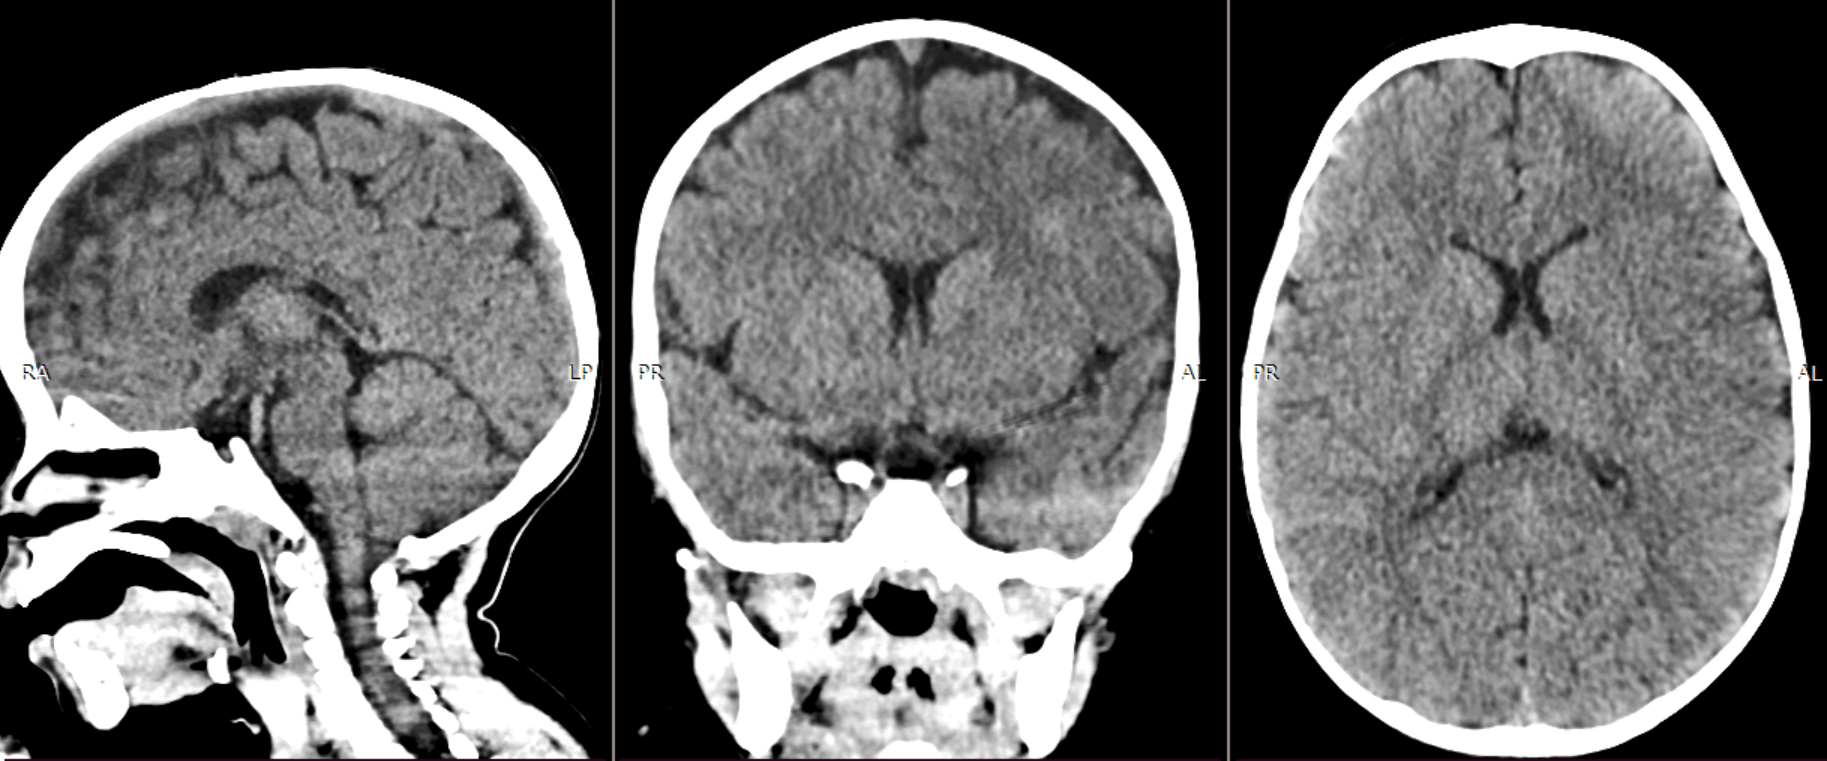

Мы живем в эпоху невероятных технологических прорывов‚ и один из самых захватывающих происходит прямо сейчас в медицине. Представьте себе: раньше‚ чтобы обнаружить крошечную опухоль в мозге‚ требовались долгие часы работы опытных врачей-радиологов‚ всматривающихся в черно-белые снимки МРТ. Теперь эту рутинную‚ но критически важную задачу может взять на себя искусственный интеллект (ИИ)‚ делая диагностику быстрее‚ точнее и доступнее. В этой статье мы поделимся нашим личным опытом разработки и внедрения ИИ для анализа изображений МРТ‚ фокусируясь на оценке опухолей мозга. Это история о том‚ как алгоритмы машинного обучения помогают спасать жизни.

Но как понять‚ что ИИ действительно научился видеть? Для этого мы использовали специальные метрики‚ такие как точность (accuracy)‚ полнота (recall) и F1-мера. Эти метрики позволяют оценить‚ насколько хорошо ИИ распознает опухоли и насколько часто он ошибается. Кроме того‚ мы использовали визуализацию результатов работы ИИ‚ чтобы увидеть‚ как он выделяет области интереса на изображениях МРТ.

Мы начали с пилотного проекта в одной из крупных больниц. Врачи-радиологи использовали ИИ для анализа изображений МРТ головного мозга‚ а затем сравнивали результаты работы ИИ со своими собственными заключениями. В большинстве случаев ИИ подтверждал заключения врачей‚ но иногда он выявлял опухоли‚ которые были пропущены при обычном анализе.